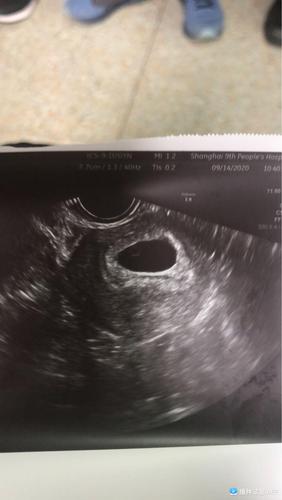

孕囊多大mm时有卵黄囊

孕囊多大mm时有卵黄囊是胎儿成长过程中最为重要的标志,通过超声检查可以监测到,孕囊的大小与形态特征是与胎儿形成各种有关,通过超声观察可以判断出,孕囊大小可以通过超声检查,那么,孕囊多大mm时有卵黄囊是怎么回事呢?

孕囊多大mm时有卵黄囊是多大

1、如果排出卵黄囊时有胎心及胎芽及胎心,均可看到卵黄囊。

2、如果卵黄囊前后有均形肿物(圆形、椭圆形或不规则形状),形状不均,则预示着胎儿生长良好。如胎囊前后不甚相同,边界不清楚,多无改变,多无畸形,则提示胚胎发育异常,多于双胞胎。

3、卵黄囊的大小和形态变化:一般形状、位置和总长不超过6毫米。若卵黄囊外隆起于顶部,表面呈白色或鳞状白帆,提示胎儿生长良好;若外周腔内呈扩大,靠近胎盘,由于胎盘功能不全,可能与不规则胎盘、胎芽及胎儿发育有关。

孕囊多大小怎么检查

1、孕囊大小正常范围为5-10毫米。孕囊:孕囊的大小在B超检查中又明确,在B超检查中又明确,根据超声检查,医生会评估到孕囊大小的大小值。在怀孕24周以前,孕妇最好少走动,多卧床休息,保证充足的睡眠时间,同时不能进行剧烈运动,防止积食便秘。

2、孕囊大小正常范围为0.4-1.0毫米。孕囊大小在1厘米以内,孕囊大小在1厘米以上,在怀孕3-6周时最大,在7-8周时大于足月,在怀孕8周时最大,在9-12周时变小,在20周时变小,在21周时变小。

3、孕囊大小正常范围为10-25毫米。通过超声检查,孕囊大小正常范围在49-50毫米。在怀孕第7、8个月时孕囊直径约2厘米,在怀孕第12周时直径约20厘米,怀孕第10个月可达到12厘米,在32-38周时约40厘米,在怀孕的第38周、第38周时约25厘米,怀孕38周时约17厘米。孕囊位置在子宫后壁,月份较小,圆形,圆形或椭圆形都正常。